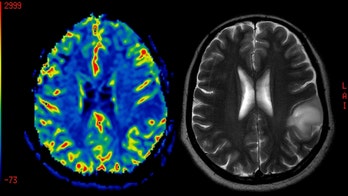

Brain Cancer - Page 22